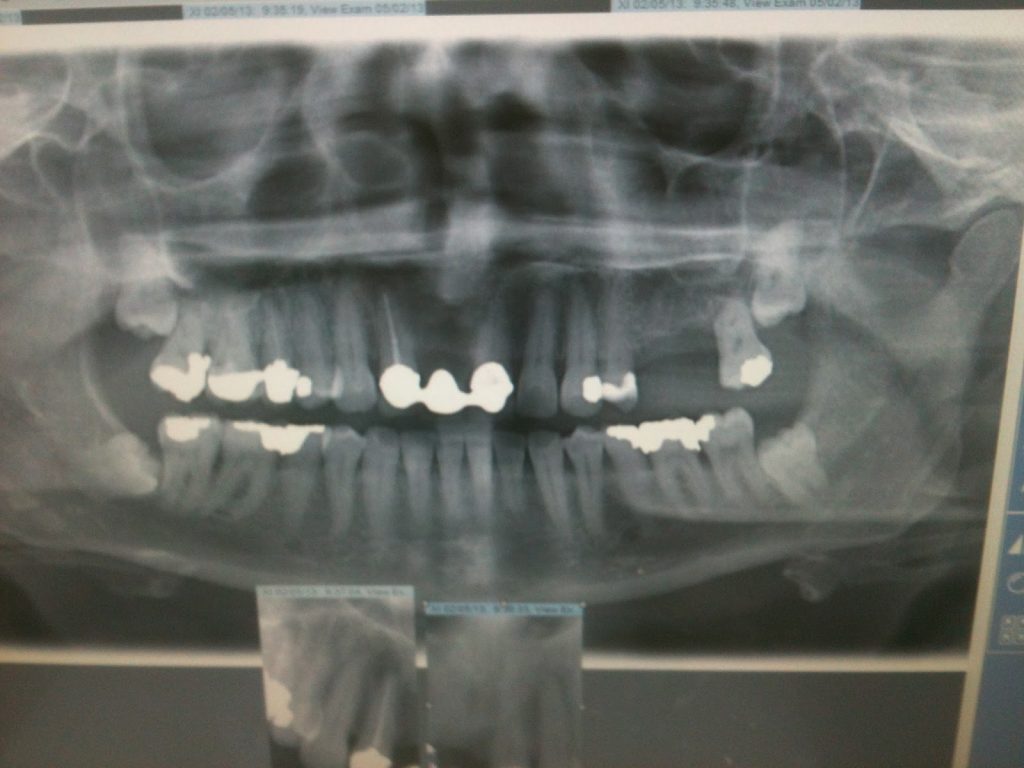

First the dentist took pictures of my teeth, then I was sent off to have several xrays taken. Then I sat in the waiting room for another 5 mins before being called in. WOW ..the technology they have is amazing. You’ve got your own monitor in front of the dentist chair. Where they then brought up all the pictures/xrays they’d taken and went through everything. they then zoomed into my crown where they showed me that I had an infection at the root of one of my teeth, where I’d had root canal treatment and where my teeth were pinned.

All very exciting but I was getting slightly nervous when they told me their plan to drill through the bridge, leaving one tooth secured and then assess whether or not they could use the supporting tooth and if so, id need to see the root canal specialist to treat the infection ..or maybe have the tooth pulled and then talk about implants …ARGHHH ..anyway, before any of the proceedings, they took moulds of my teeth so they could build a temporary plate for me, so I wouldnt be toothless 😀

So, after a 30 minute wait and mulling over a price plan. I went back into see the dentist.. by this time my hands were pretty sticky ….we talked about the options again and then he set to work ..drilled through my bridge, took 2/3 of it out and then checked the tooth underneath ..urgh, it looked rank ..even the picture makes me squirm. As the tooth wasnt that stable, he decided it should be pulled. So off to another section I went. Injected 3 times and mulling about in the chair for what seemed a life time, the pull commenced ..took ages and I was more concerned about her putting pressure on my remaining tooth, crowny thing. Finally, it was out and she gave me a couple of dissolvable stiches …then a massive piece of gauze to bite on, to stop the bleeding …by this time I couldn’t speak and muttered a thank you and left and headed straight back into see the other dentist where he pulled out this temporary plate and then proceeded to show me how to insert/take it out …wow, that was quick.